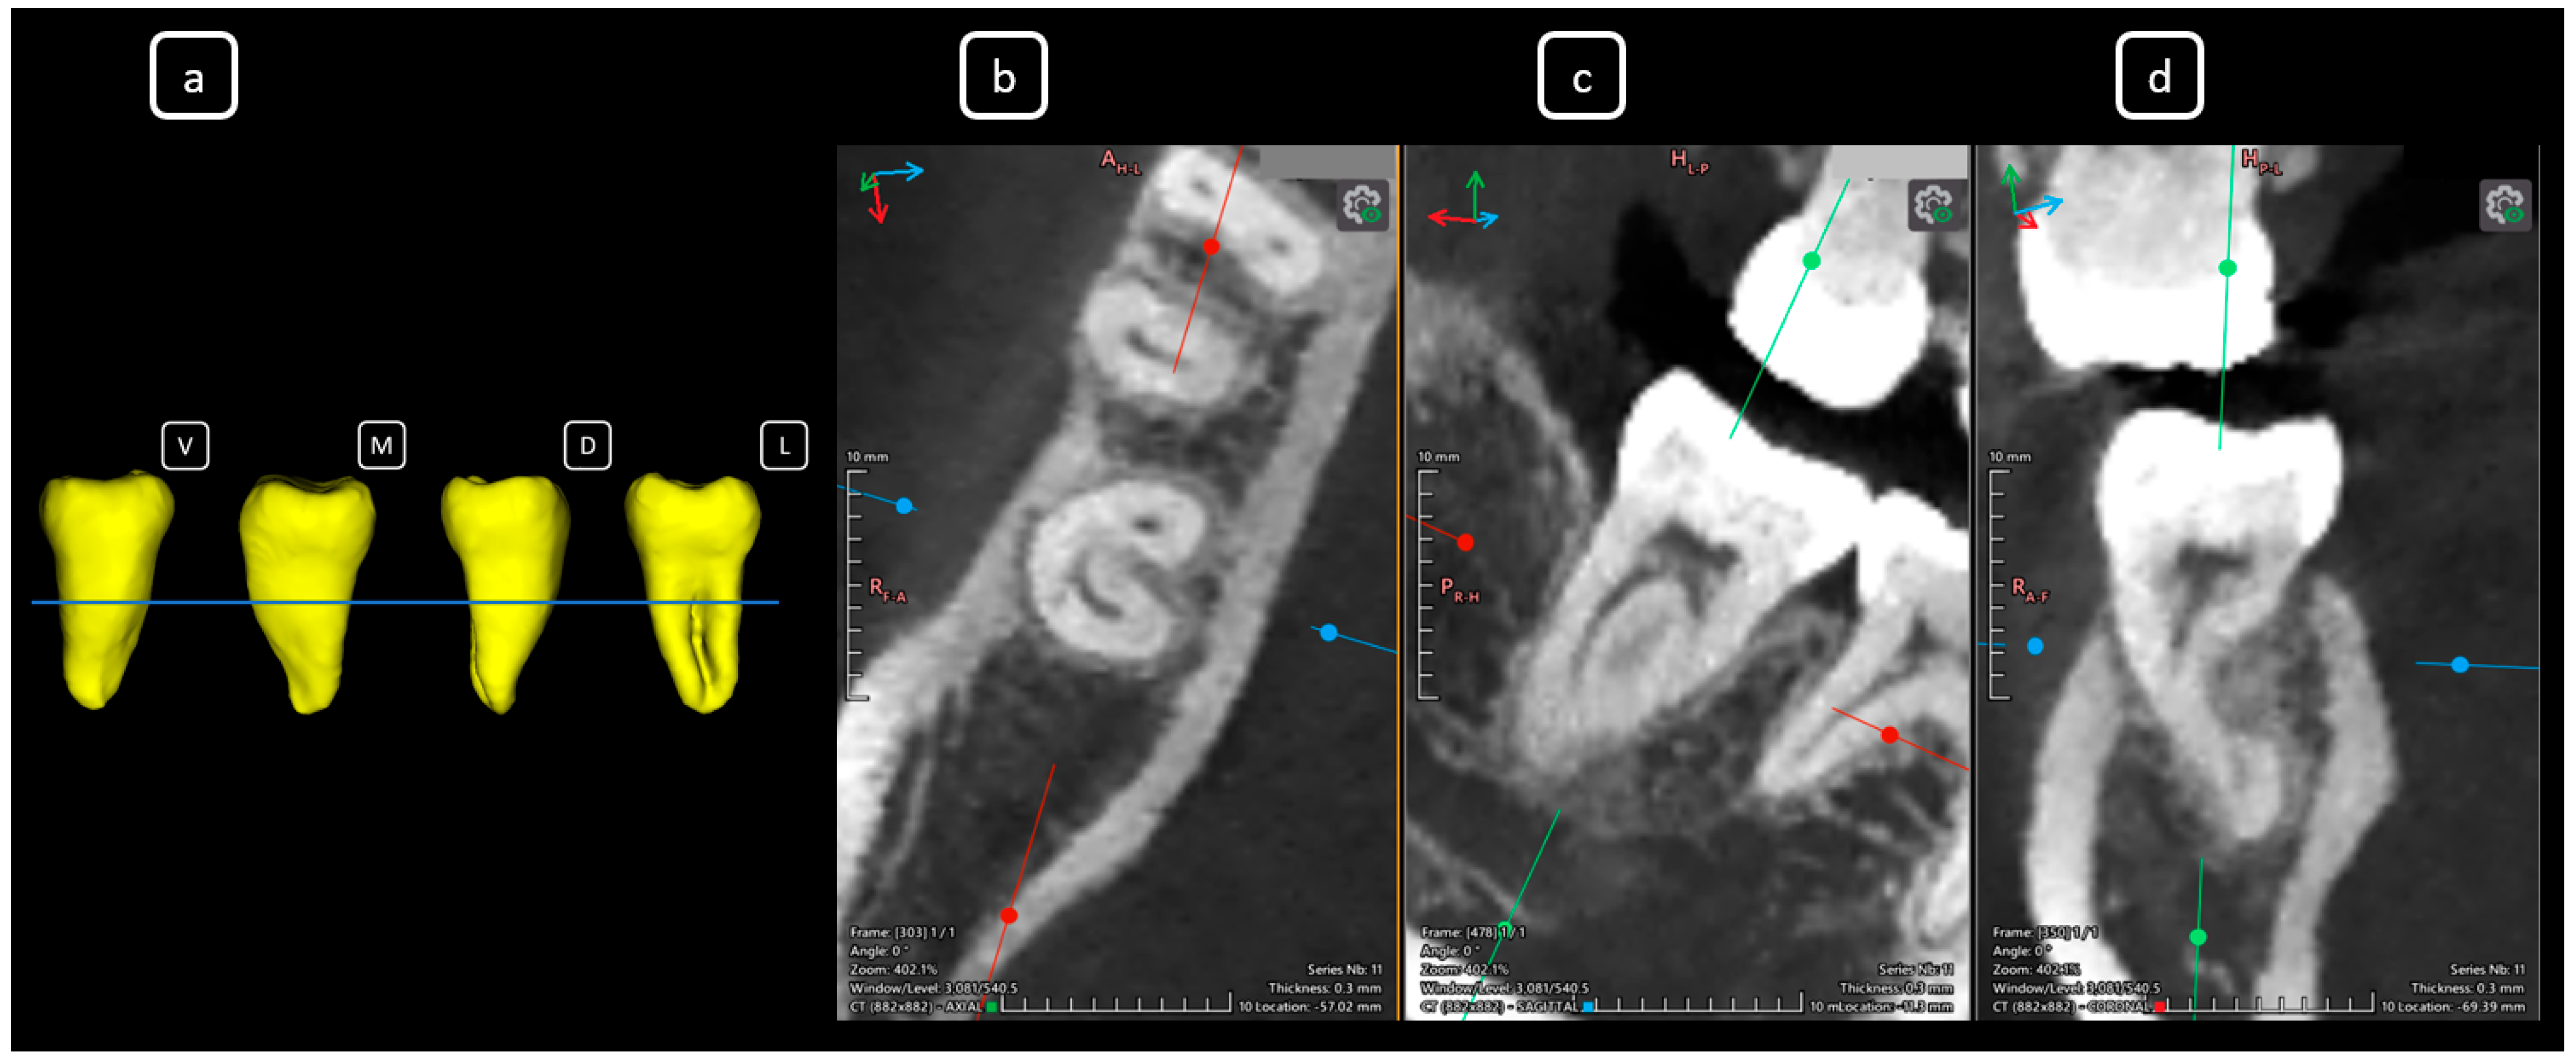

Imaging Findings of Clinical Significance in Endodontics During Cone Beam Computed Tomography Scanning of the Upper Airway—The Anterior, Bilateral, C-Shaped, Dual of Mandibular Root Canals: A Brief Case Report

García-Torres, E.; Guerrero-Falcón, D.L.G.; Bojórquez-Armenta, H.A.; Almeda-Ojeda, O.E.; Barajas-Pérez, V.H.; Solís-Martínez, L.J. Imaging Findings of Clinical Significance in Endodontics During Cone Beam Computed Tomography Scanning of the Upper Airway—The Anterior, Bilateral, C-Shaped, Dual of Mandibular Root Canals: A Brief Case Report. Diagnostics 2025, 15, 3157. https://doi.org/10.3390/diagnostics15243157